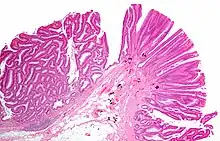

| Tubulovillous adenoma (tubular component – left of image, villous component – right of image). H&E stain. | |